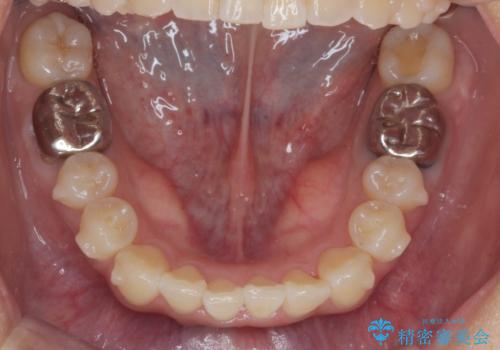

正中のズレ、引っ込んだ前歯の矯正

- 噛んだ時の前歯正中のズレ、引っ込んでいる前歯を治したい。と矯正治療を希望され来院されました。

左上2の前歯はスペースが足りないため、後方に引っ込んでしまっている状態です。

マウスピース矯正システムインビザラインで歯の後方移動、咬合関係の修正を行ったのち、引っ込んでいる左上2をワイヤーを用いて短時間で引き出す治療計画としました。

部分ワイヤー矯正を行なったことで約3ヶ月という短期間で前歯を綺麗に並べることができました。